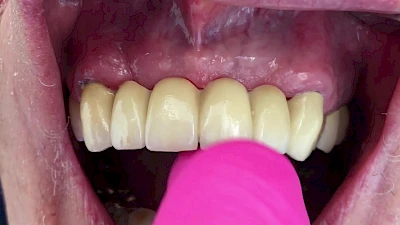

Eine geringe spürbare Beweglichkeit der Zähne ist durchaus normal, da Zähne über Fasern im Kieferknochen aufgehängt sind. Lassen sich Zähne, Kronen oder Brücken jedoch deutlich sichtbar bewegen, besteht die Gefahr, dass sie sich lösen und verschluckt oder aspiriert werden. Deshalb sollte in diesen Fällen der Zahnarzt verständigt werden.